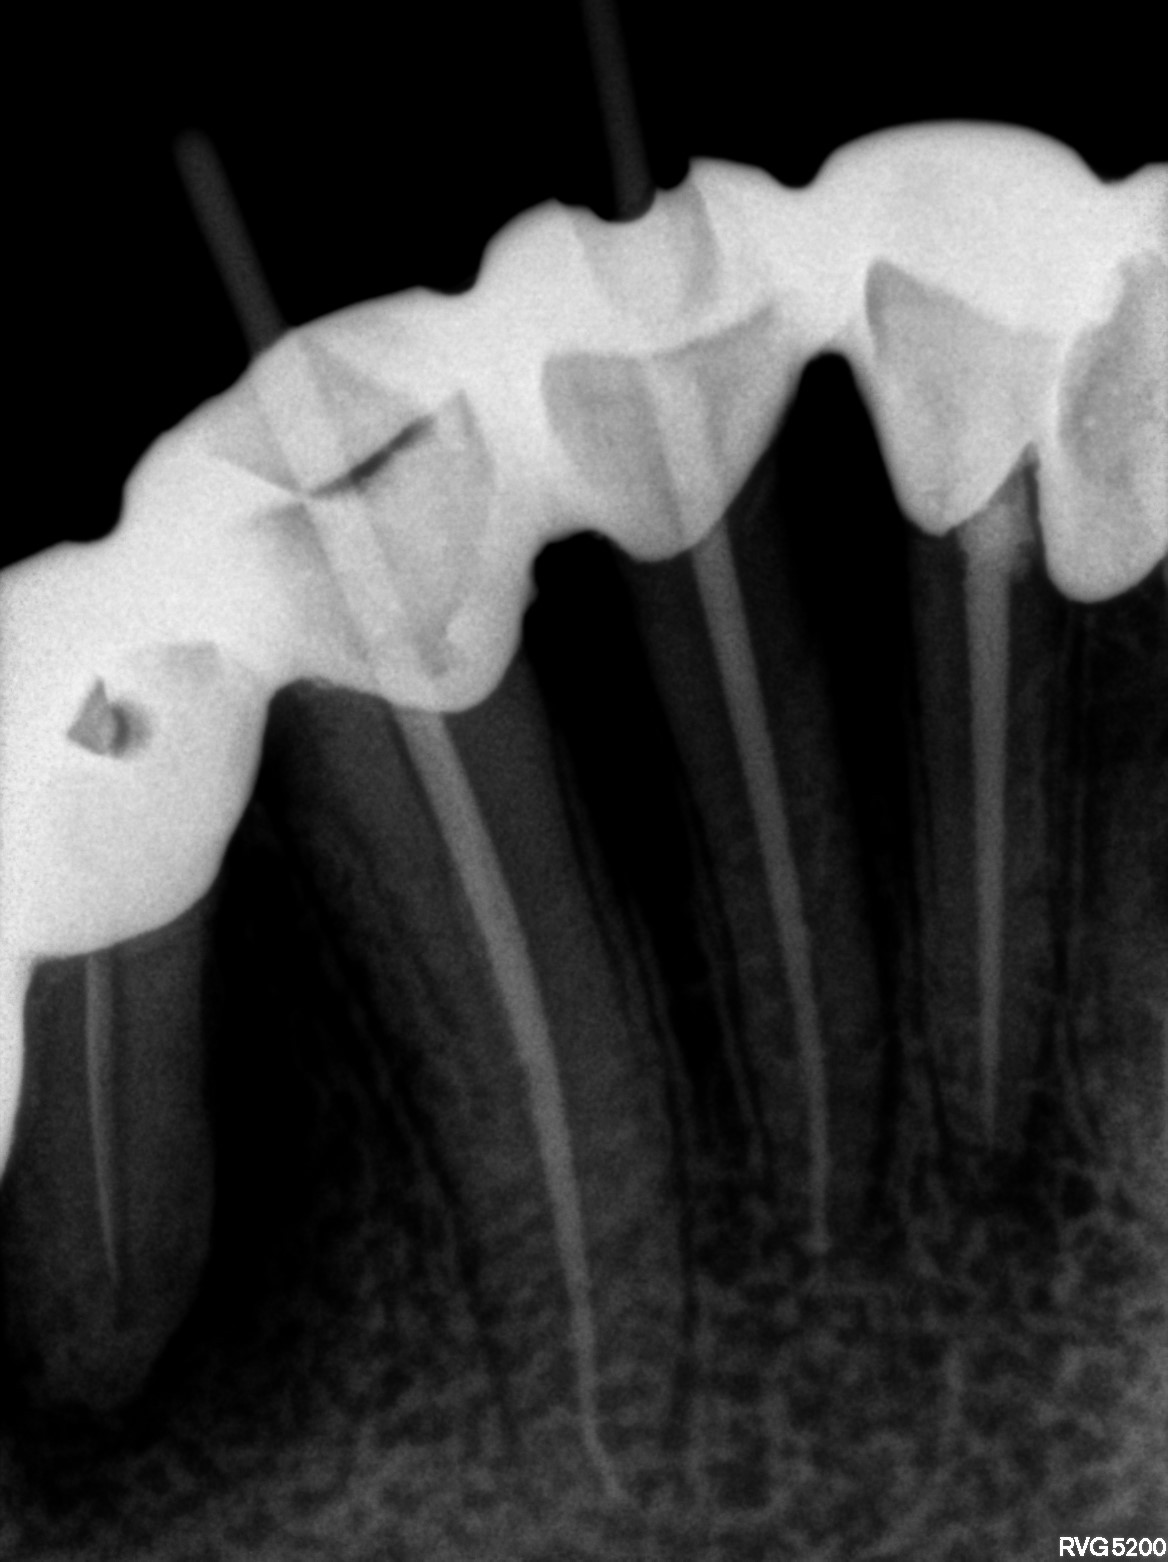

Dental Radiographs FHIR: DocumentReference · LOINC 24641-7

xray_1763362538_4.jpg

24641-7